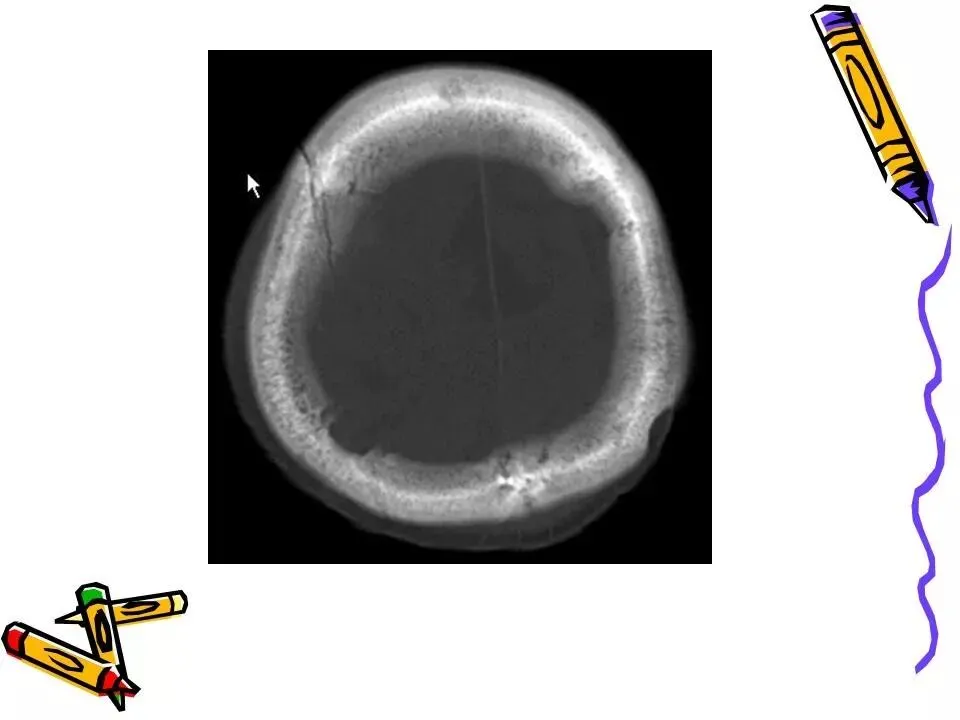

>常见颅脑外伤CT诊断(PPT)

常见颅脑外伤CT诊断(PPT)